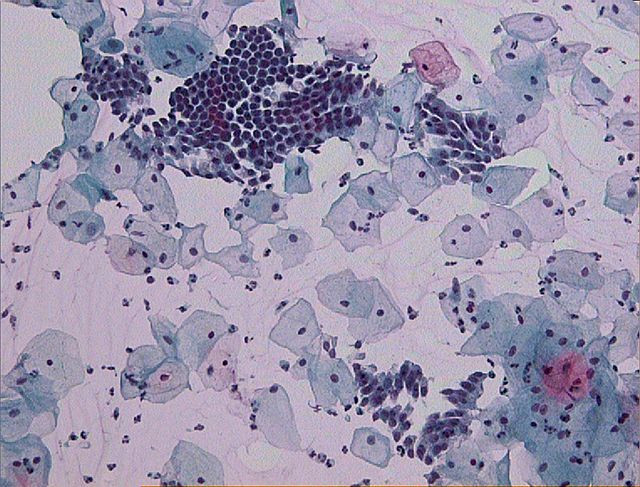

Kitajska raziskovalna skupina je z analizo DNK brisov materničnega vratu določila vrstno sestavo bakterij, ki so bile del vaginalne mikrobiote pri 45 neokuženih in 90 ženskah, okuženih s HPV. Izkazalo se je, da več ni vedno bolje. Kitajske znanstvenice in znanstveniki so najmanjšo vrstno pestrost določili v mikrobioti neokuženih žensk. Vrstna pestrost je bila višja pri posameznicah s trajno okužbo v primerjavi s posameznicami s prehodno okužbo.

Pri neokuženih v mikrobioti dominira ena bakterija iz rodu Lactobacillus. Znano je, da laktobacíli vzdržujejo nizek pH v nožnici, kar otežuje naselitev drugih bakterij, pa tudi okužbo celic povrhnjice materničnega vratu z virusom HPV. Pri dobri polovici okuženih posameznic je kitajska raziskovalna skupina odkrila, da je dominantna vrsta bakterije prav tako iz rodu Lactobacillus. Pri ostalih okuženih pa je bila dominantna bakterijska vrsta iz drugega rodu, predvsem Sneathia in Prevotella

Vir slike: https://upload.wikimedia.org/wikipedia/commons/thumb/d/d6/Pap_test_wnl…